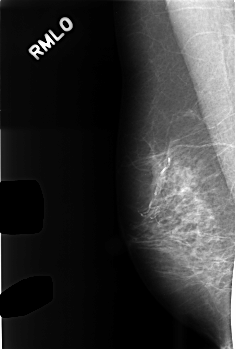

C_0476_1.RIGHT_MLO

RIGHT_MLO LINES 4536 PIXELS_PER_LINE 3064 BITS_PER_PIXEL 12 RESOLUTION 50 NON_OVERLAY